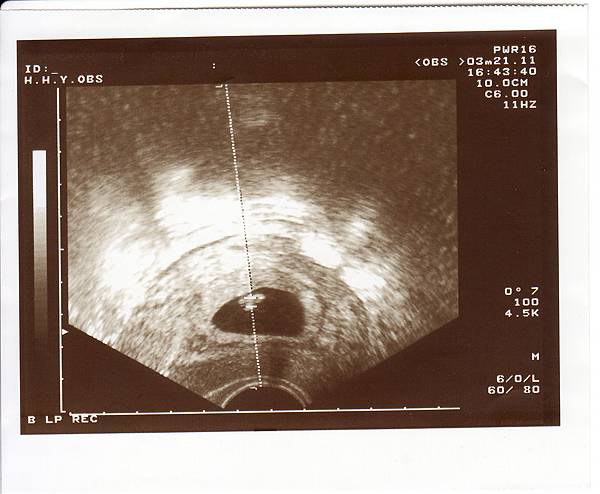

2011.03.21 聽見悅耳的心跳聲,心中的大石也終於放下